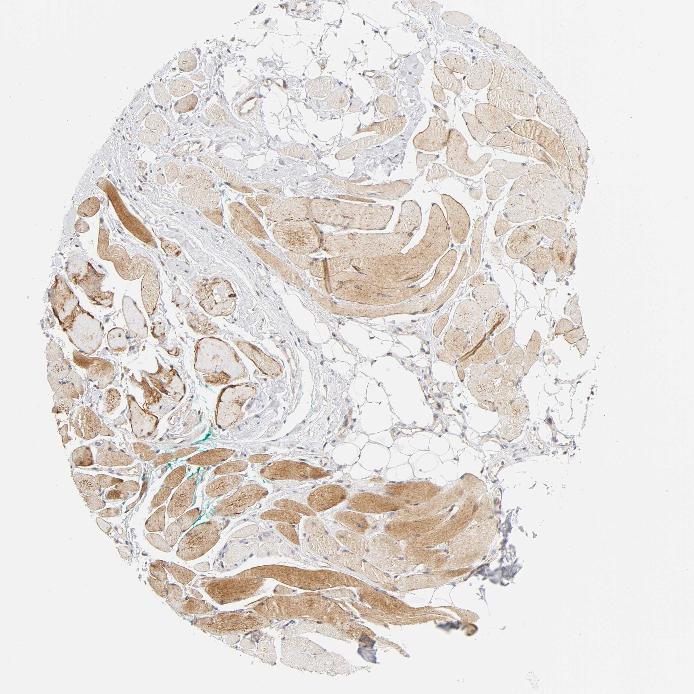

SKELETAL MUSCLE - Antibody stainingi

Antibody staining in the annotated cell types in the current human tissue is reported as not detected, low, medium, or high, based on conventional immunohistochemistry profiling in selected tissues. This score is based on the combination of the staining intensity and fraction of stained cells.

Each image is clickable and will lead to virtual microscopy that enables deeper exploration of all samples and also displays staining intensity scores, fraction scores and subcellular localization as well as patient and tissue information for each sample.

Antibody CAB004312

Myocytes Medium